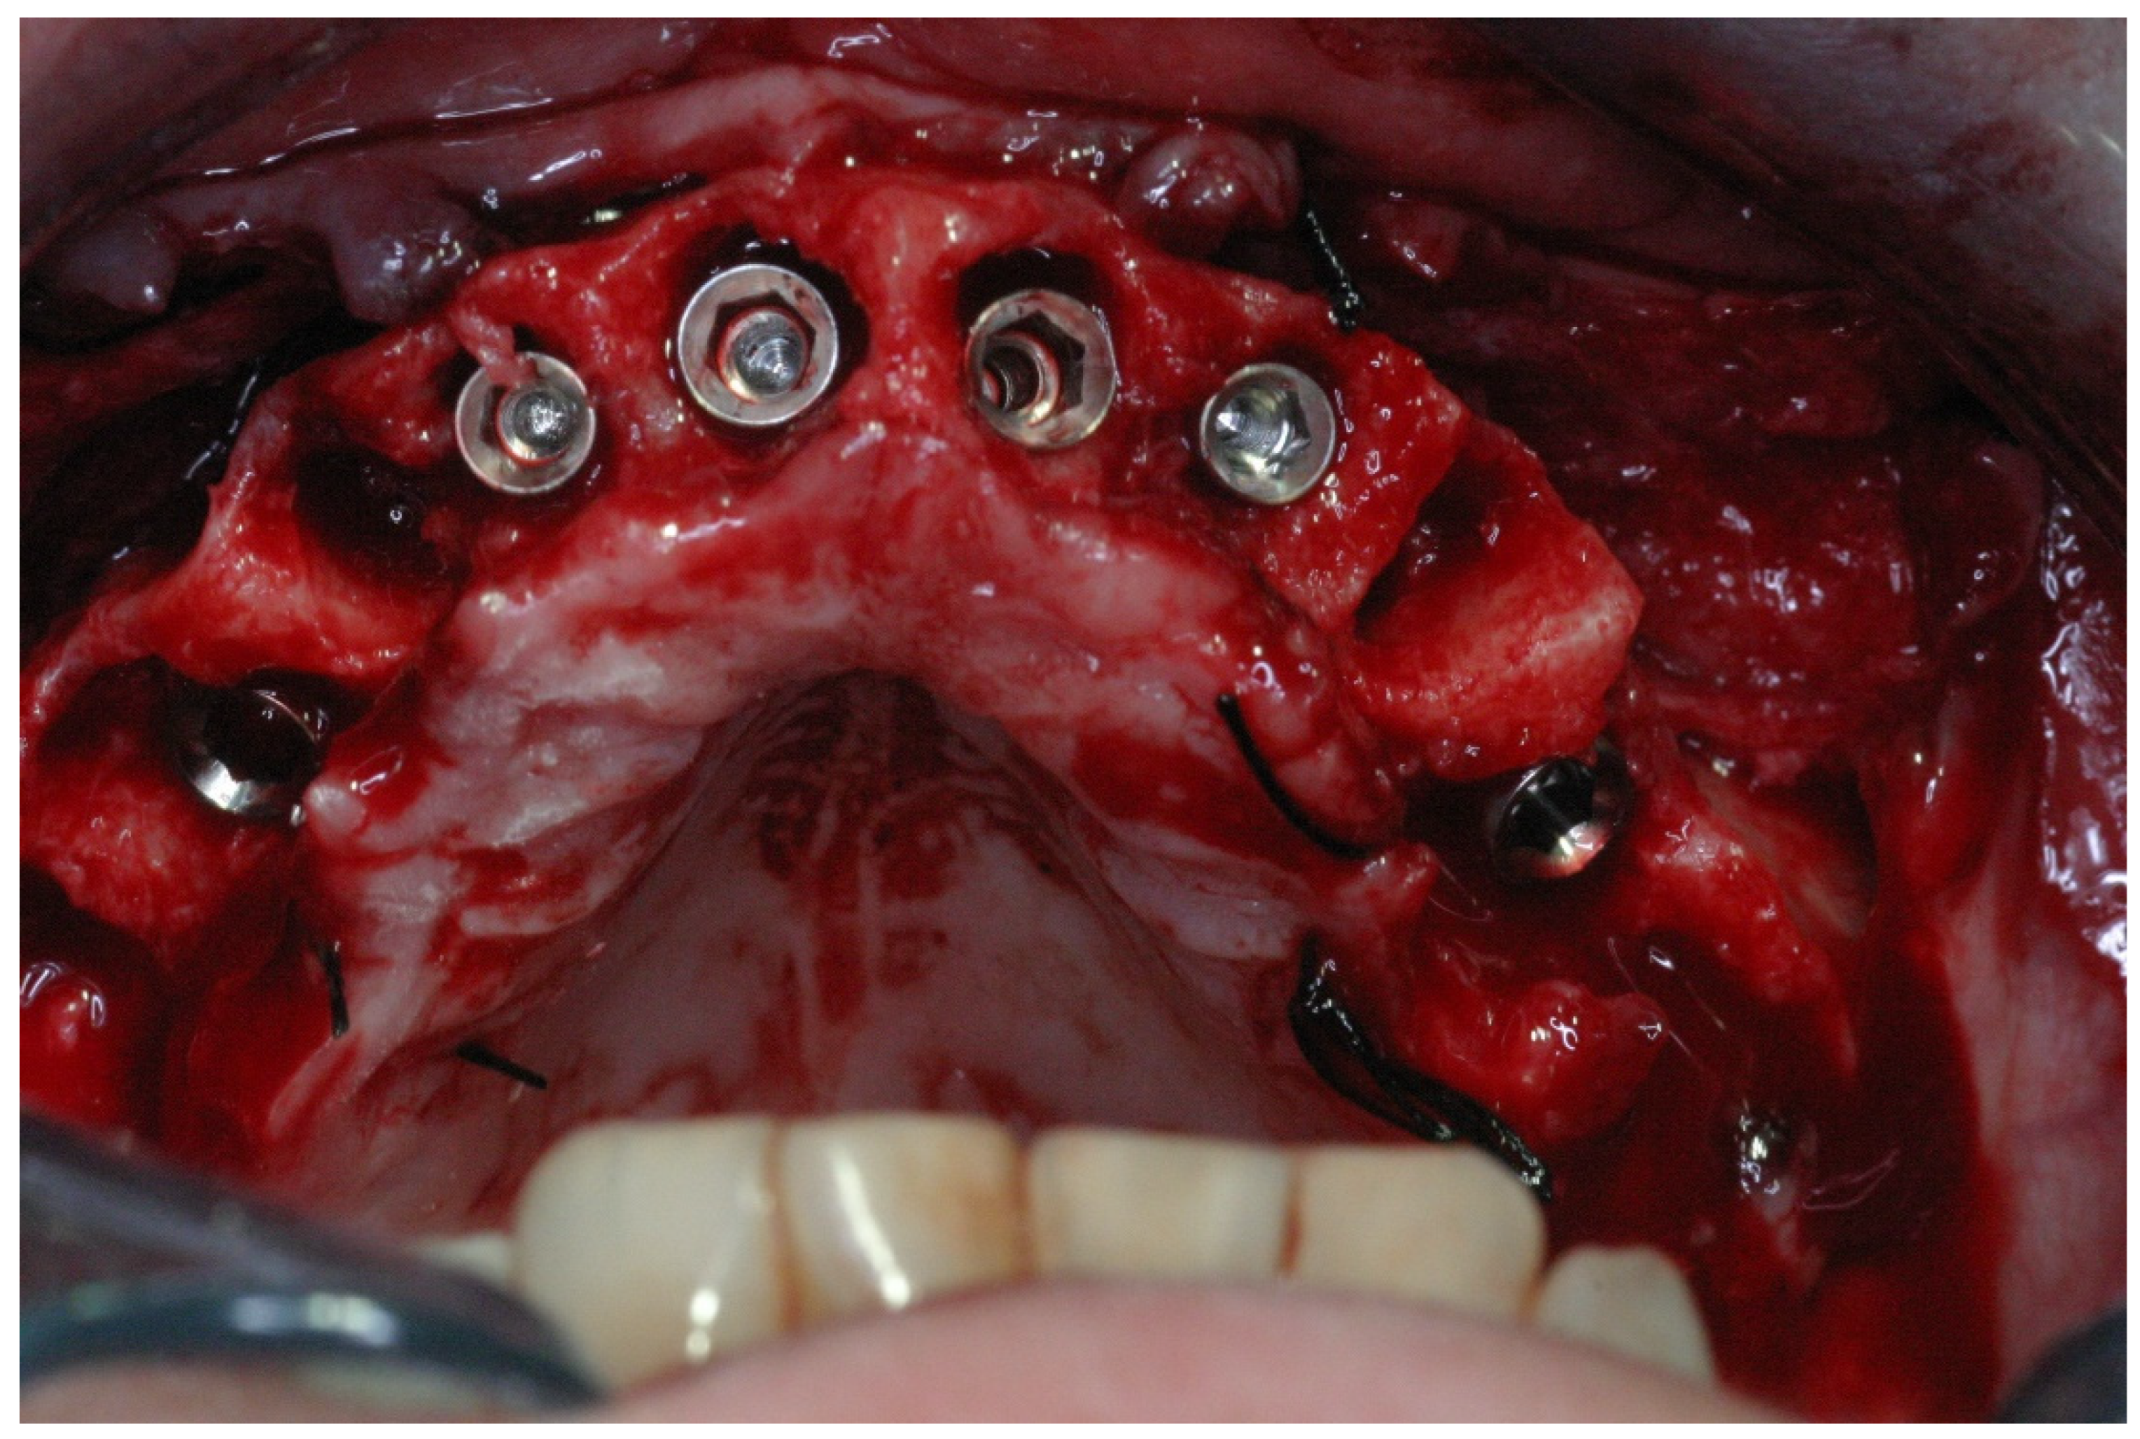

2.2. Surgical Treatment